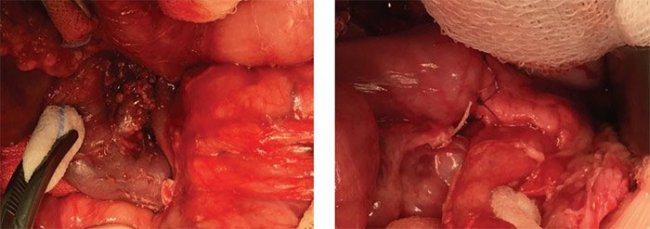

При предположительно фокальной форме гиперинсулинизма по данным генетического обследования и ПЭТ/ КТ после раскрытия полости малого сальника поджелудочную железу тщательно осматривают и пальпируют, чтобы попытаться визуализировать очаговое поражение. В ряде случаев очаги определяются визуально в виде округлых дополнительных выступов (рис. 13, 14), при этом, в отличие от инсулином, они не имеют плотной капсулы и сохраняют визуально дольчатую структуру поджелудочной железы; другие определяются в виде плотных на ощупь участков в толще железы; третьи ни визуально, ни пальпаторно определить не представляется возможным.

Рисунок 13. Интраоперационная картина: фокусы аденоматозной гиперплазии видны визуально на задней поверхности головки железы, справа – в области тела

Рисунок 14. Интраоперационная картина: фокусы аденоматозной гиперплазии видны визуально в области тела

железы